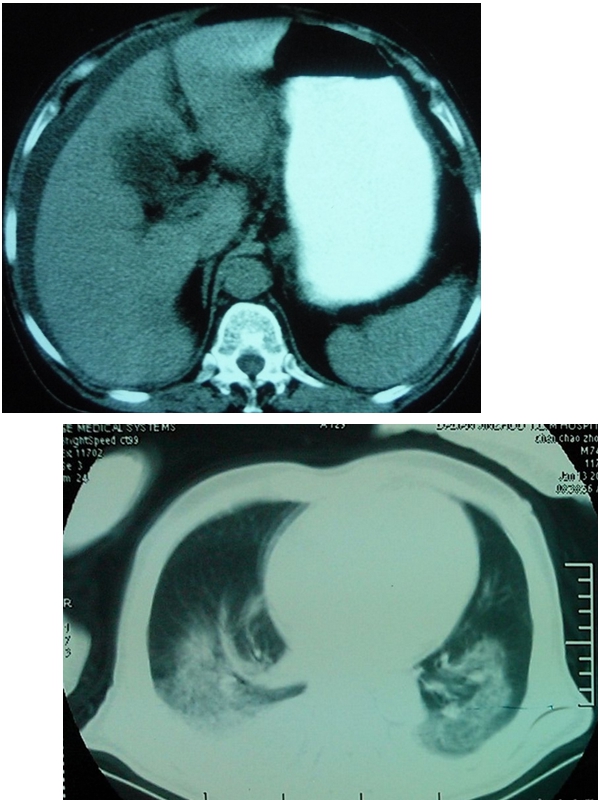

胸水腹水鑑別ct